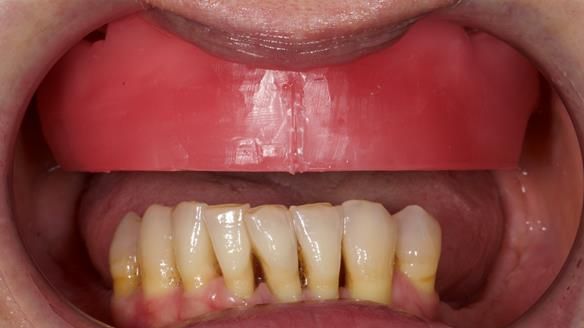

We provided her with an immediate upper denture (Mk 1), followed by a definitive metal-based upper denture (Mk 2). A lower removable partial denture was discussed, to be made only if needed once the upper treatment was complete. However, at review, this wasn’t necessary — Adnana had excellent neuromuscular control and function, even with a shortened dental arch (SDA).

- Definitive denture (Mk 2), metal-based and custom-designed for her face

- A restored smile, restored lip support, and a patient who owned the journey